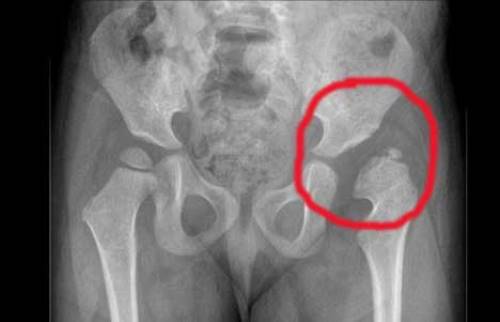

Диагностика подвывиха тазобедренного сустава обычно включает клинический осмотр, а также рентгенографию для визуализации положения суставных поверхностей. В некоторых случаях может потребоваться МРТ для более детального изучения мягких тканей и суставных структур.